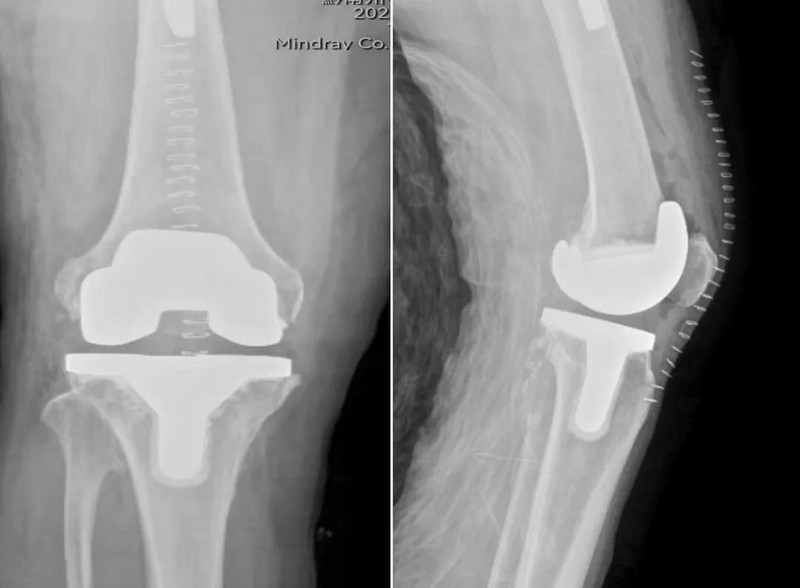

人工关节植入步骤指南

概述人工关节是一种医疗技术,用于替换因疾病、损伤或其他原因而失去功能的关节,本步骤指南旨在帮助读者了解人工关节的相关知识,包括其必要性、种类、手术过程及术后康复,无论您是初学者还是进阶用户,通过阅读本文,您将了解如何...